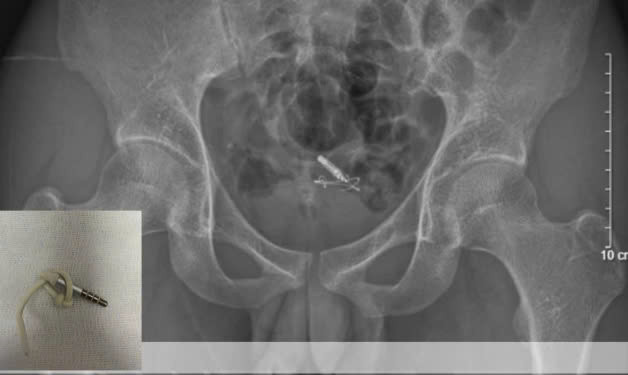

| Kết quả chụp X-quang và siêu âm cho thấy dị vật nằm trọn trong bàng quang. Ảnh BVCC |

Tại bệnh viện, các bác sĩ khoa Nam học và Y học Giới tính, đã xác định đây là trường hợp dị vật gây tổn thương niệu đạo. Kết quả chụp X-quang và siêu âm cho thấy dị vật nằm trọn trong bàng quang.

Ê-kíp đã tiến hành nội soi gắp dị vật thành công, lấy ra một đoạn dây cáp tai nghe kèm 1 jack cắm 3.5mm dài khoảng 10cm, bảo tồn nguyên vẹn cấu trúc bàng quang và niệu đạo.